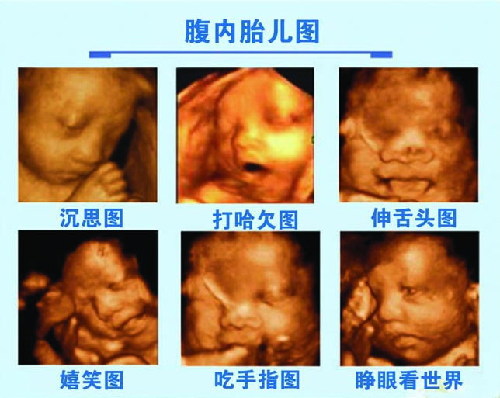

什么时候做四维彩超好?城阳玛丽妇儿医院专家表示,很多孕妈妈都想提前看看自己的宝宝可爱的样子,然而四维彩超的好处并不只是为了满足准妈准爸们的好奇心,它还是是目前监测宝宝健康状况先进的手段之。

什么时候做四维彩超好?专家指出,只要有适量的羊水就可以做四维彩超,但往往会有很多的因素影响,比如:胎儿的体位、胎盘、还有不同的孕期、羊水等因素,所以,建议在25-28周做四维彩超好。

温馨提示:以上就是专家对什么时候做四维彩超好?的相关介绍,专家指出,四维彩超诊断仪是目前上先进的彩色超声设备,它能实时获取三维图像并超越了传统超声的限制。如果孕妈妈们想要提前了解更多关于宝宝的信息,不妨到医院做次四维彩超检查。